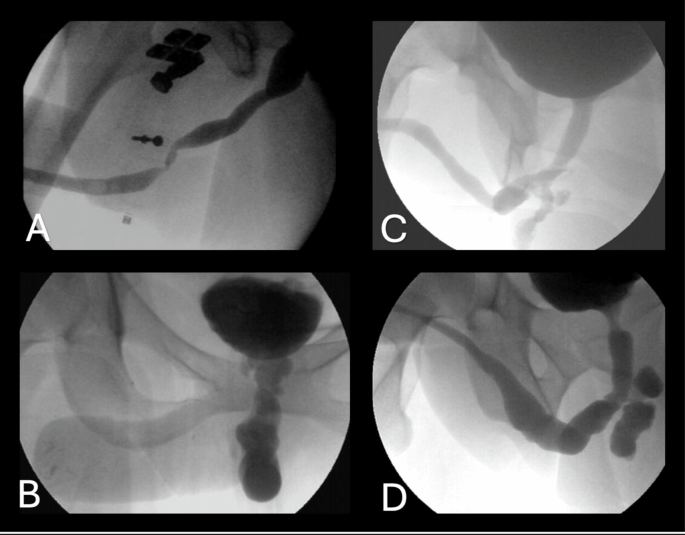

To provide a clearer understanding of the outcomes from various studies, Fig. 2 presents an example of UL anatomy following phalloplasty, while Fig. 3 illustrates examples of urethral complications. Several urethroplasty techniques were employed across studies, including single-stage [9, 17, 18] and staged repairs [19, 20], buccal mucosa graft urethroplasty (BMGU) [7, 17, 21], excision and primary anastomosis (EPA) [22], pedicled flaps [23], Heineke-Mikulicz procedure (HMP) [23,24,25] and ventral meatotomy [26].

In this systematic review, we analyzed a total of 585 urethroplasty procedures performed primarily in transmen, mostly following phalloplasty, with a smaller number occurring after metoidioplasty. In rare instances, outcomes of urethroplasty in cisgender men were included in the reported data. The urethra in phalloplasty is often constructed using a combination of local mucosal flaps for the pars fixa and skin flaps or grafts for the pars pendulans, creating a structure composed of different types with varying supportive tissues and healing capacities. The urethra in metoidioplasty is often constructed using a combination of local mucosal flaps, with adjunction of BMG or vaginal mucosa graft; this approach closely resembles the construction of the pars fixa in phalloplasty. The main complications arise from the distal urethral anastomosis and the pars pendulans, where skin is commonly used. In contrast, BMG is the preferred graft material for redo urethroplasty [28].